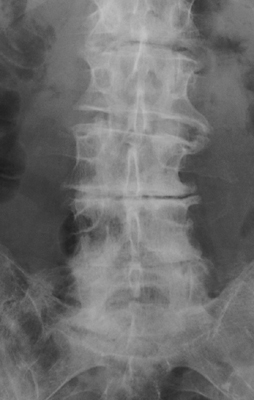

Vacuum Phenomenon

Degenerative disk disease

The presence of a linear radiolucency in the disk space (vacuum phenomenon) is a typical finding of degenerative disk disease. It is often associated to other findings of degenerative disk disease such as disk space narrowing and endplate sclerosis. Gas in the disk space is rarely associated to disk space infection.